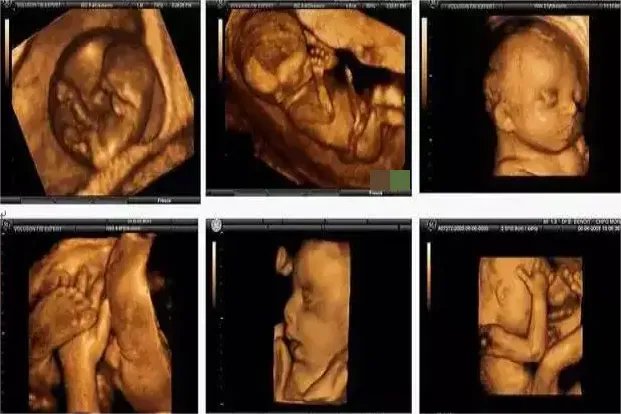

彩超可清晰显示胎儿五官、四肢、各器官的发育情况,对胎儿畸形,如唇裂、腭裂、骨骼发育异常、心血管畸形等能早期发现并诊断。四维彩超甚至可以直观的看到胎儿在母体里的状态、胎动过程等。

长沙百佳玛丽亚妇产医院郝淑艳主任表示,孕妈妈做四维彩超检查如果处于饥饿状态下或者宝宝不配合,是会出现拍不到宝宝脸的情况。有的时候,孕妈妈调节一下可以看到宝宝的脸,但有的时候孕妈妈需要隔天或再次做四维彩超才能和宝宝相见。而在玛丽亚做四维彩超的孕妈们不要担心,如果出现四维彩超拍不到宝宝脸的情况,玛丽亚是可以再次拍或者隔天拍的哦。